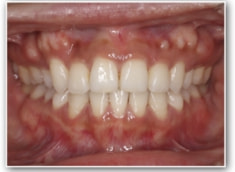

叢生+左下1番先天欠如ケース

治療法:裏側の矯正(リンガルブラケット:舌側矯正)

治療後